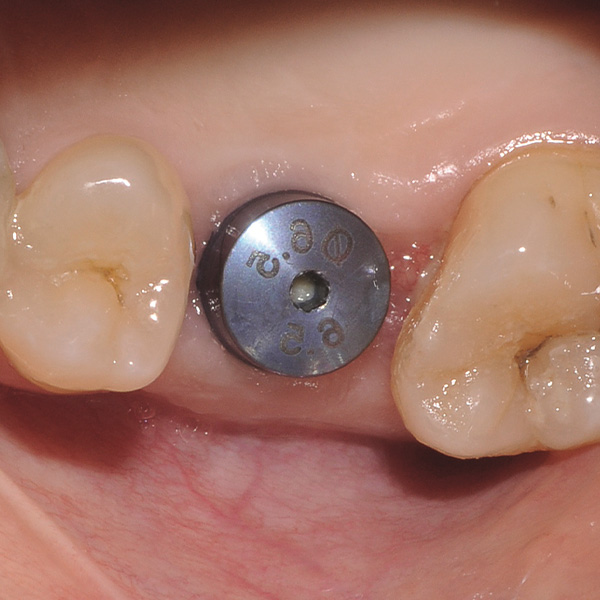

Restauri supportati da impianti sono soggetti a carichi particolarmente elevati. Dopo l‘estrazione e l‘impianto al paziente manca l‘apparato di fibre elastiche del letto dentale naturale. Per questo motivo le forze di masticazione non vengono assorbite, ma trasmesse direttamente sul restauro, l‘impianto, l‘osso e la dentatura antagonista. La ceramica ibrida VITA ENAMIC ha una struttura a reticolo duale in ceramica (86 % in peso) e polimero (14 in peso). Ne risulta un‘elasticità simile alla dentina e la capacità do assorbire le forze di masticazione. Il blocchetto policromo VITA ENAMIC multiColor in geometria EMC-16, grazie alla sua elevata dimensione verticale, consente di realizzare corone-abutment monoblocco, monolitiche anche nel caso di osso atrofizzato. L‘odontoiatra Professor Dr. Alexander Hassel mostra in questo contributo come riabilita una paziente con questa forma di restauro.